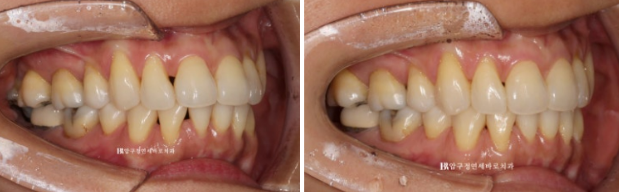

23.04~23.08

비스듬한 측면에서 봤을 때에도 블랙트라이앵글이 많이 줄어든 것이 보입니다.

치간삭제와 고무줄을 병행하면서 튀어나와있었던 앞니를 뒤로 꽤 많이 넣었습니다.